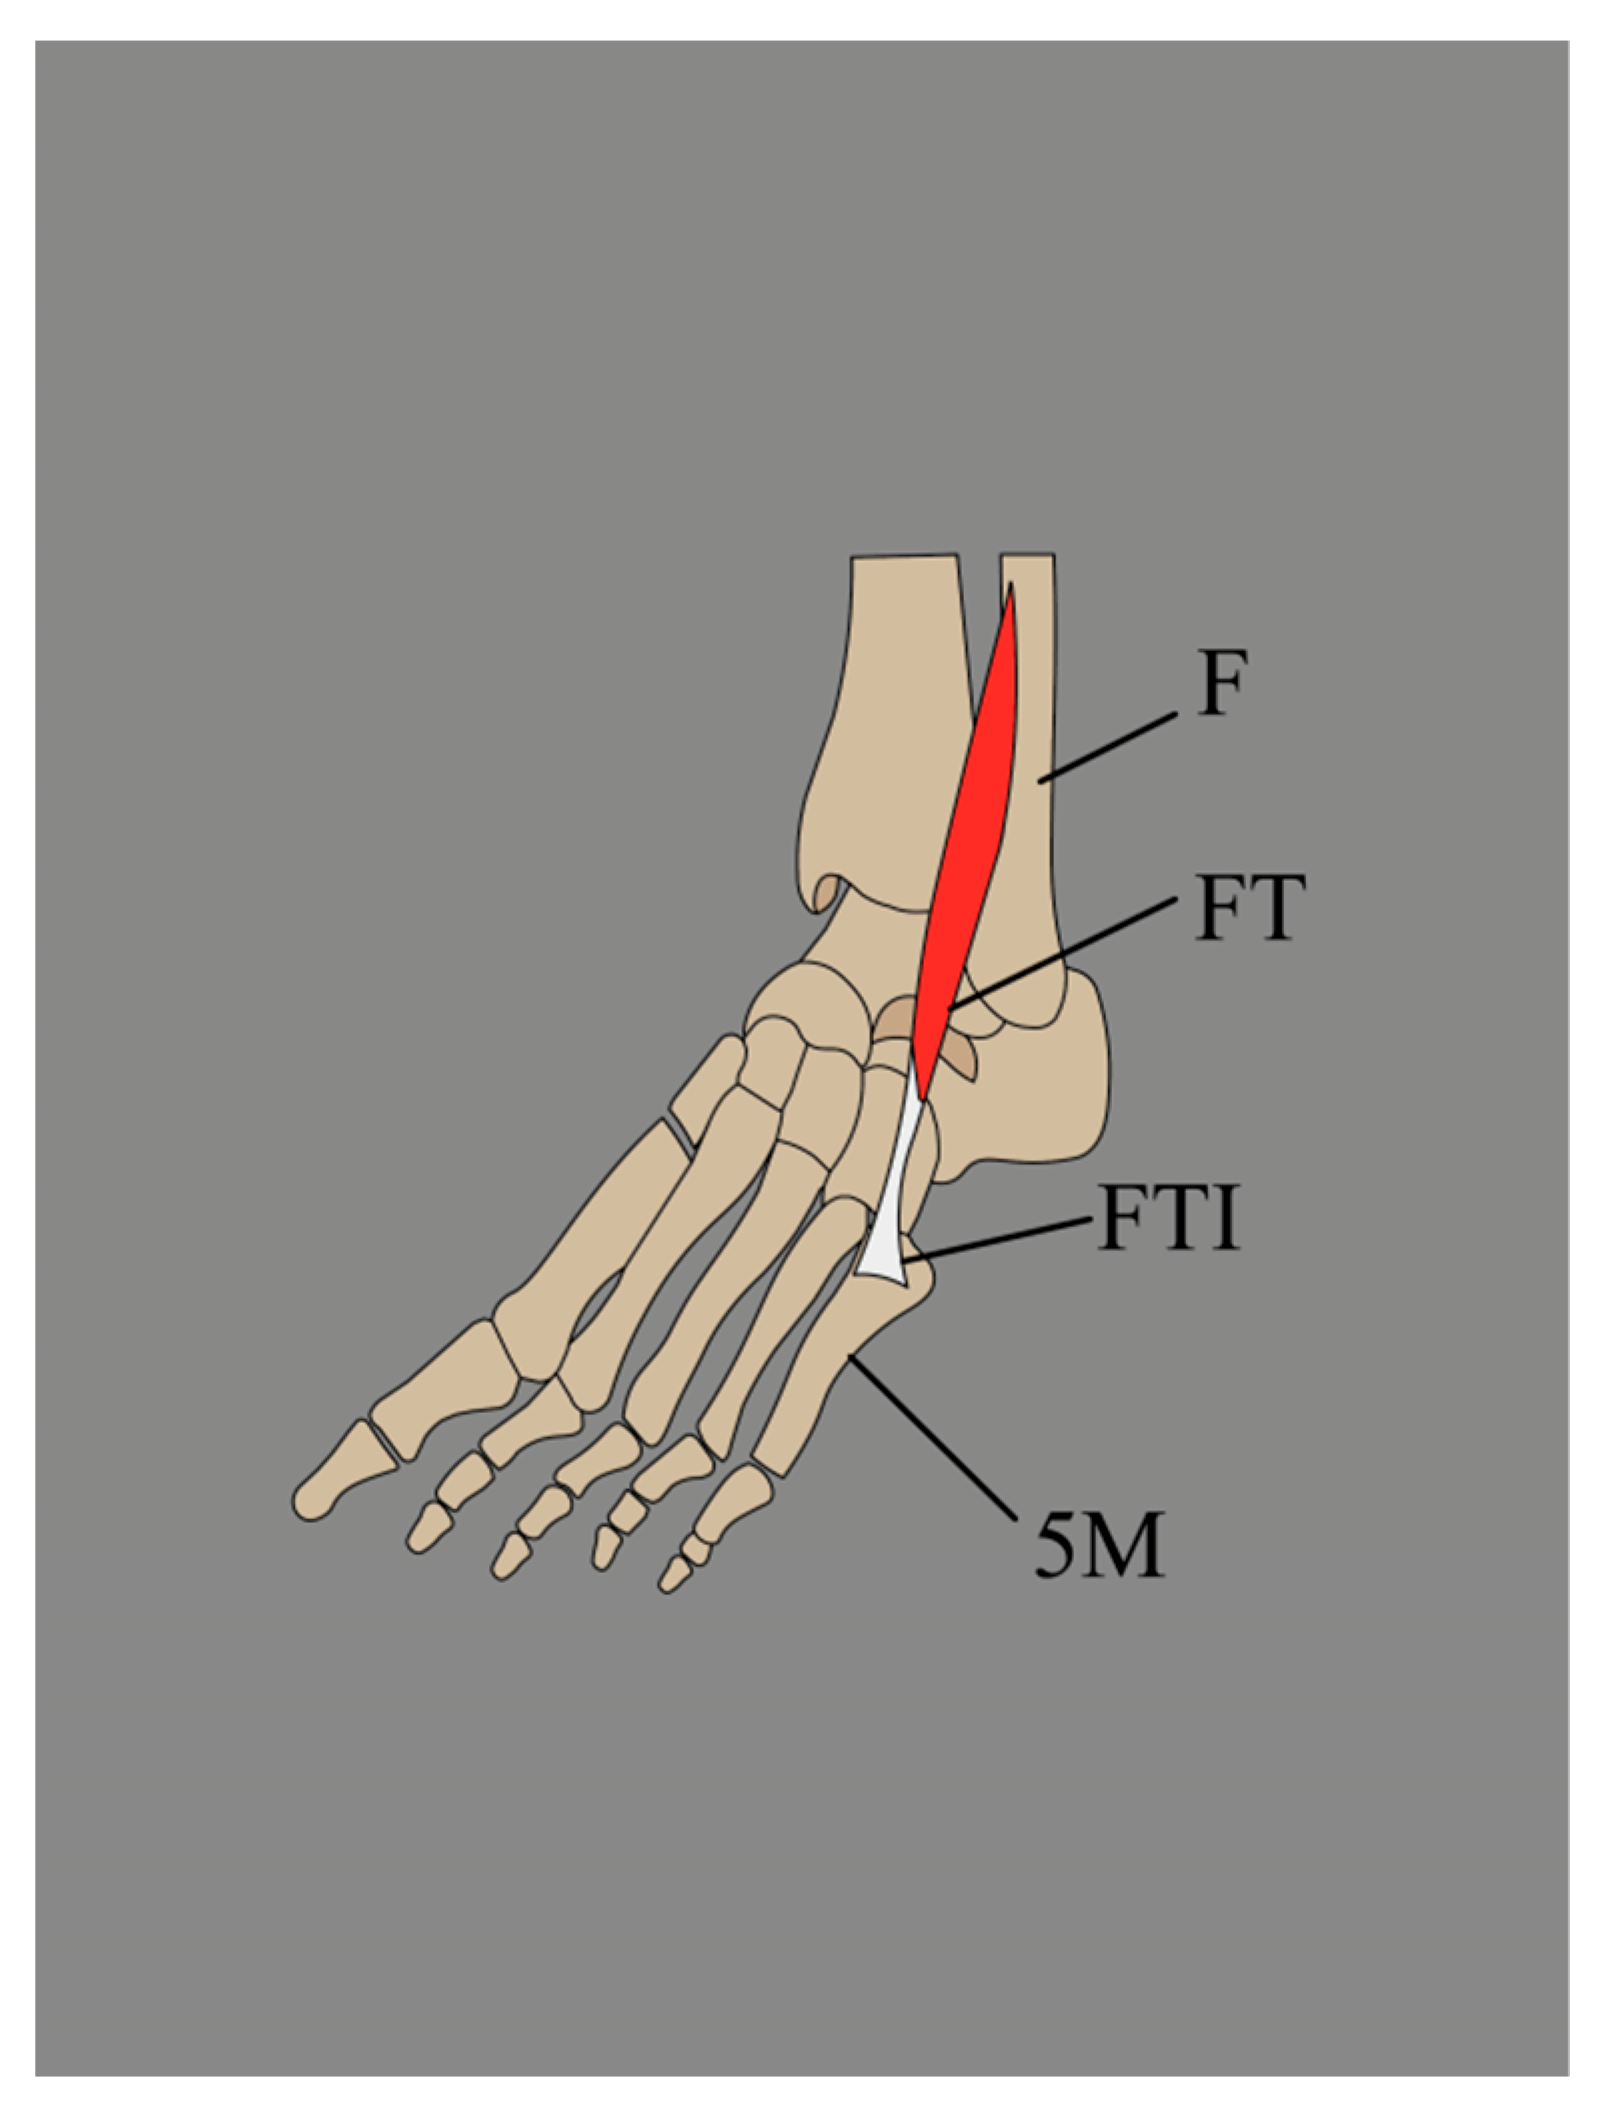

3.2.3. Variations in the Insertion of the Fibularis Tertius (FT)

- A single tendon, band-shaped, inserted into the shaft of the fifth metatarsal bone (45%).

- A single tendon, fan-shaped, inserted at the base of the fifth metatarsal bone (22%).

- A single tendon, fan-shaped, inserted into the fascia covering the fourth interosseous space and the base and shaft of the sixth metatarsal bone (16.5%).

- A bifurcated tendon consisting of both band and fan shapes. The main fan-shaped tendon is inserted at the base of the fifth metatarsal bone, while the accessory tendon is attached to its shaft (8.8%).

- A bifurcated tendon, fan-shaped, where the main tendon is inserted at the base of the fifth metatarsal bone, and the secondary tendon attaches to the base of the fourth metatarsal bone (5.5%).

- This tendon fuses with an additional band from the FB, which gives rise to the fourth interosseous dorsalis muscle (2.2%).

3.2.4. Fibularis Tertius Tendon (FTT) Morphology